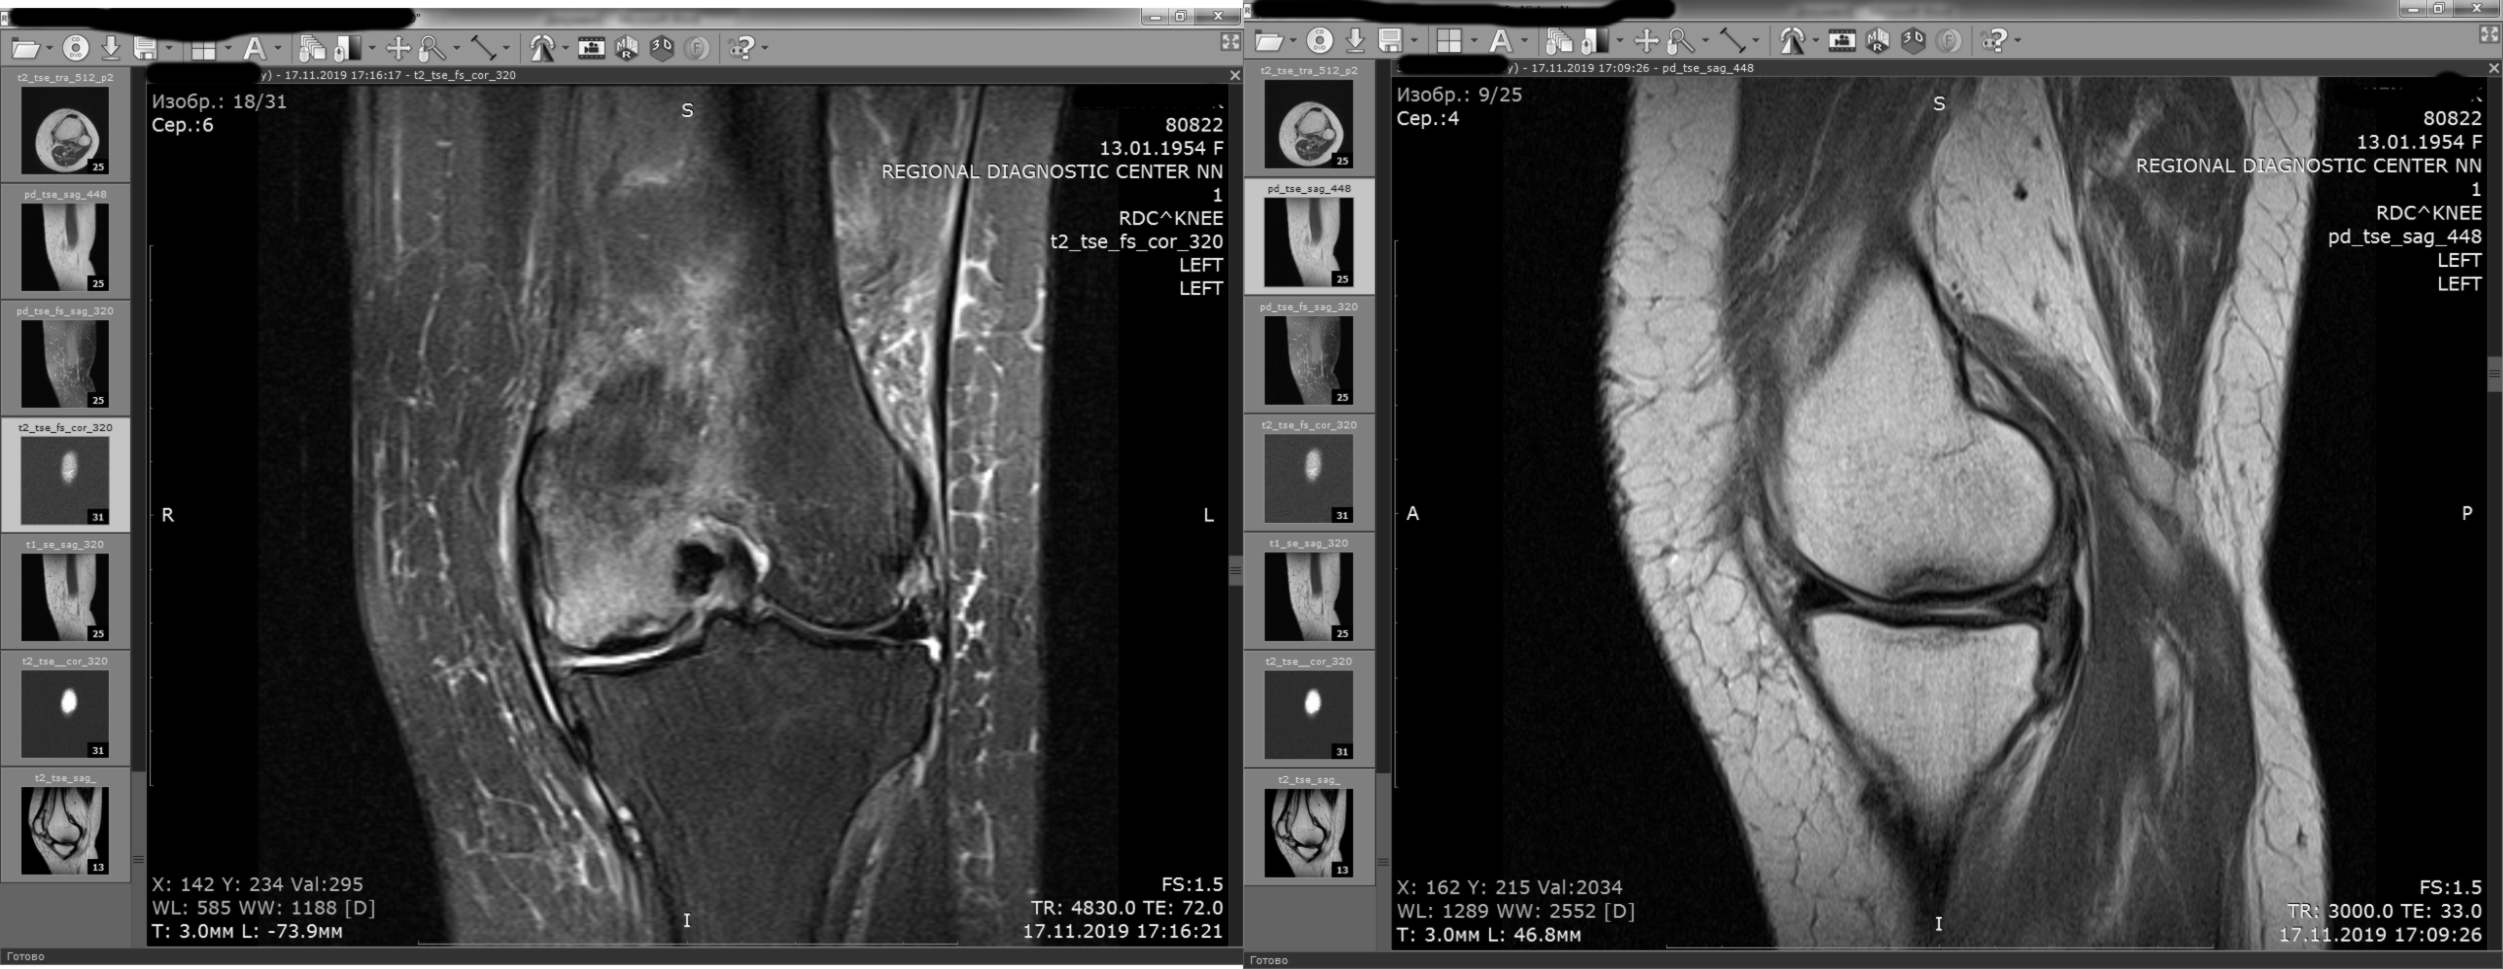

Прилагаю избранные сканы МРТ до операции

|